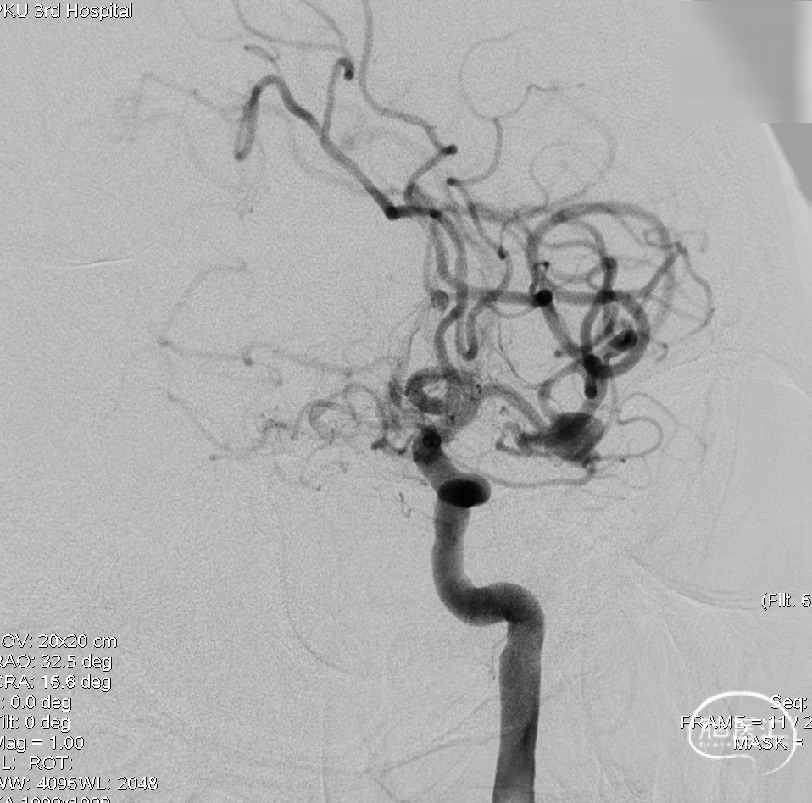

术前影像学检查:术前正侧位。

术前工作位与三维重建:显示右侧MCA分叉部未破裂动脉瘤,6.9mm*7.2mm,瘤颈7.4mm。该病例之困难在于M1迂曲成袢。